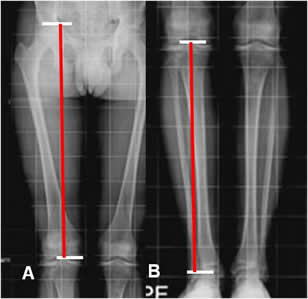

Las dismetrías se pueden calcular, con: (1, 2, 3, 8). (Fig 102).

Los puntos de referencia para hacer la medición son el borde superior de la cabeza femoral, el borde inferior del cóndilo femoral medial, la eminencia intercondílea tibial y el borde inferior de la tibia. (1, 2, 3). (Fig 103).

Fig 103. Longitud de extremidades.

A y B: Rx simple. Medición de las extremidades. En el fémur desde el borde superior de la cabeza femoral, hasta el borde inferior del cóndilo medial y en la pierna desde la eminencia intercondilea, hasta el borde inferior de la tibia.

Fig 105. Acortamiento.

Rx AP. Acortamiento de la extremidad izquierda, sin encontrar lesiones focales y secundario a disminución en la longitud de la tibia.

En cuanto al tratamiento las diferencias menores de 15 mm, generalmente no requieren manejo. Las mayores de 15 mm se tratan con plantillas y mayores de 3-4 cm, con zapatos ortopédico. Por encima de 5 cm se utiliza el alargamiento del miembro mas corto. (3). (Fig 107 y 108).

Fig 107. Tratamiento.

Rx AP con plantilla. Acortamiento izquierdo, que disminuye utilizando una plantilla,

aunque persiste elevación de la cabeza femoral derecha y el desbalance pélvico.

Fig 108. Uso de alzas.

A: Telemétrica sin alza y B: Telemétrica con alza. Paciente con luxación abandonada de la cadera derecha (No mostrada) y acortamiento secundario de la extremidad. El uso de la alza en B, disminuye la diferencia de 5 cm a 3.5.